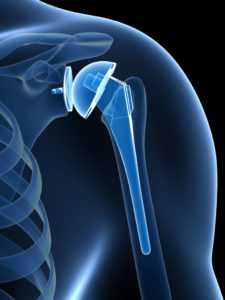

Reverse Shoulder Replacement:

In Reverse Total Shoulder Replacement, the socket and metal ball are switched. That means a metal ball is attached to the Shoulder Bone and a plastic socket is attached to the humerus. This allows the patient to use the deltoid muscle instead of the Torn Rotator Cuff to lift the arm.